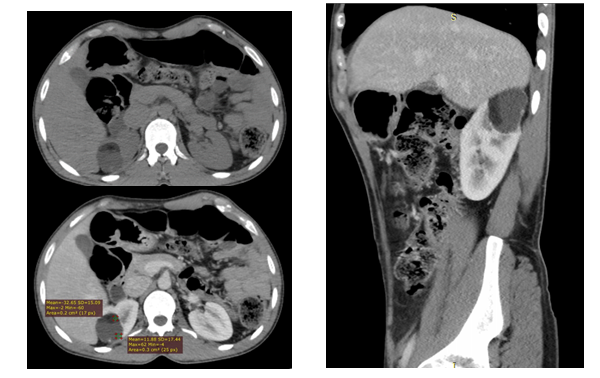

A 58-year-old man presented with history of flank pain. Physical examination showed no palpable masses. Laboratory investigations were in the normal range. Ultrasonography (US) revealed a well circumscribed 4.8 x3.6 x 3.7 cm mass arising within the upper pole of the right kidney (Figure 1). The mass consisted of predominantly hypoechoic portion which demonstrated posterior acoustic enhancement. There is also a hyperechoic component overlaying the cystic portion with fat fluid level suggesting the diagnosis of dermoid cyst. Pre and post IV contrast abdominal CT done with 128 slice CT machine reveled 4.8 x 3.8 x 3.7 cm well circumscribed mass in the upper pole of the right kidney (Figure 2). The mass had a fat attenuation component overlaying the predominant fluid attenuation component with clear fat fluid level. No calcification was seen which confirmed the diagnosis.

Figure 2: Axial pre and post contrast and coronal post contrast images demonstrating a mass in the upper pole of the right kidney with a fat fluid level.